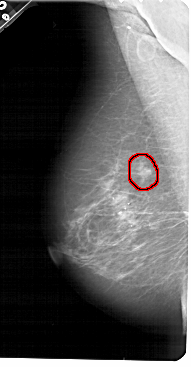

A_1442_1.LEFT_MLO

LEFT_MLO LINES 5491 PIXELS_PER_LINE 2851 BITS_PER_PIXEL 12 RESOLUTION 43.5 OVERLAY

FILE: A_1442_1.LEFT_MLO.OVERLAY

TOTAL_ABNORMALITIES 1

ABNORMALITY 1

LESION_TYPE MASS SHAPE OVAL MARGINS ILL_DEFINED

ASSESSMENT 4

SUBTLETY 3

PATHOLOGY BENIGN

TOTAL_OUTLINES 1

BOUNDARY